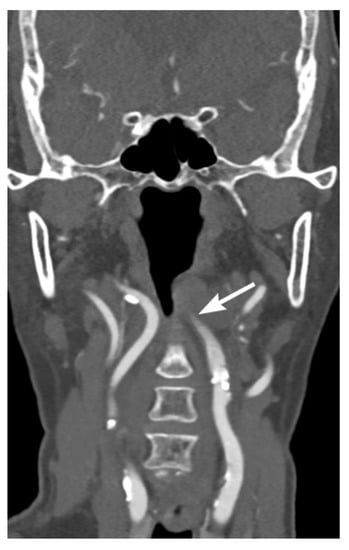

3. Imaging Findings of Arterial Injury